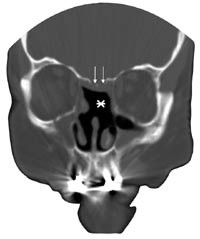

Pasient 1. En 61 år gammel kvinne ble operert på grunn av kronisk sinusitt. Etter operasjonen rant det klar væske fra nesen og lekkasjen økte når hun bøyde seg fremover. Væsken inneholdt 42 mg/l betasporprotein, en verdi som er forenlig med likvoré. CT-undersøkelsen viste en beindefekt i sentrale lamina cribrosa. Det kunne ikke avgjøres om det forelå en ensidig eller en bilateral lekkasje. Hun ble operert endoskopisk med natriumfluoresceinfargeteknikk. Under operasjonen fant man lekkasje på begge sider av lamina cribrosa, og defektene ble dekket med frie transplantater av fascia lata (fig 1).